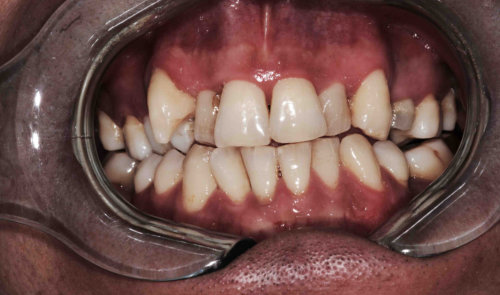

Oberkiefer-Frontzähne (Zähne12-22) Keramikverblendkronen Situation vorher Situation nachher

Brücke rechts oben, ab mittlerem Schneidezahn (Zähne 14 -11) Situation vorher Situation nachher